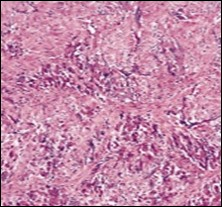

On microscopy, a collagen- rich, minimally cellular, fibrotic soft tissue nodule is exemplified which simulates a scar or conventional fibroma. The neoplasm is comprised of uniform, plump, fibroblastic or myo-fibroblastic cells encompassed in a collagen-rich stroma with infiltration and entrapment of skeletal myocytes 5, 6. Cogent histological examination depicts replacement of muscle fibres and muscle mass with fascicles of fibrous tissue comprised of mature fibroblastic cells, thereby conferring fibrosis 6. Figure 1, Figure 2, Figure 3, Figure 4, Figure 5, Figure 6, Figure 7, Figure 8.

Figure 1.Fibromatosis colli depicting bundles of fibroblasts and myo-fibroblasts intermixed with a collagenous stroma and entrapped myocytes 9.

Figure 2.Fibromatosis colli demonstrating fascicles of fibroblasts and myo-fibroblasts within an abundant collagenous stroma and several mature myocytes 10.